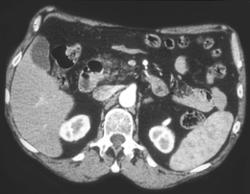

Diagnosis

Hepatic Aa Off Aorta